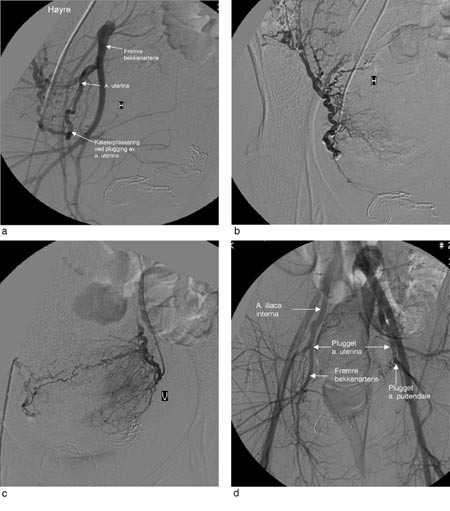

Etter tre timer med manuell kompresjon var det fortsatt profus blødning og uterusatoni. Pasientens trombocyttall hadde falt til 74 · 10⁹/l, og hun ble overflyttet til angiografilaboratorium. Høyre femoralarterie ble punktert og et 1,7 mm innføringskateter lagt inn. Under gjennomlysning ble et endehullskateter ført ned i høyre uterinarterie (fig 1) Gelfoam ble klippet i biter på 3 · 3 mm og bløtt opp i en blanding av kontrastmiddel og saltvann. Uten videre diagnostikk ble høyre uterinarterie plugget med partiklene. Deretter ble samme kateter lagt ned i venstre uterinarterie og arterien plugget. Angiografi av bekkenarteriene viste ingen tegn til blødning. På dette tidspunkt var uterusatonien opphevet og uterus godt kontrahert. Pasienten var hemodynamisk stabil. Kompressene i vagina ble fjernet, og ved inspeksjon var det fortsatt en del blødning. På mistanke om blødning fra vagina-cervix-området ble det utført angiografi av a. obturatoria og a. pudendalis bilateralt. Det ble ikke funnet direkte eller indirekte tegn til blødning. Flere av grenene forsynte rectum og blæren. En tilsynelatende normal venstre a. pudendalis ble plugget, da den forsynte området for mistenkt blødning. Etter emboliseringen fortsatte uterus å være godt kontrahert, og det var sparsom blødning. Dagen etter var trombocyttallet steget til 162 · 10⁹/l.